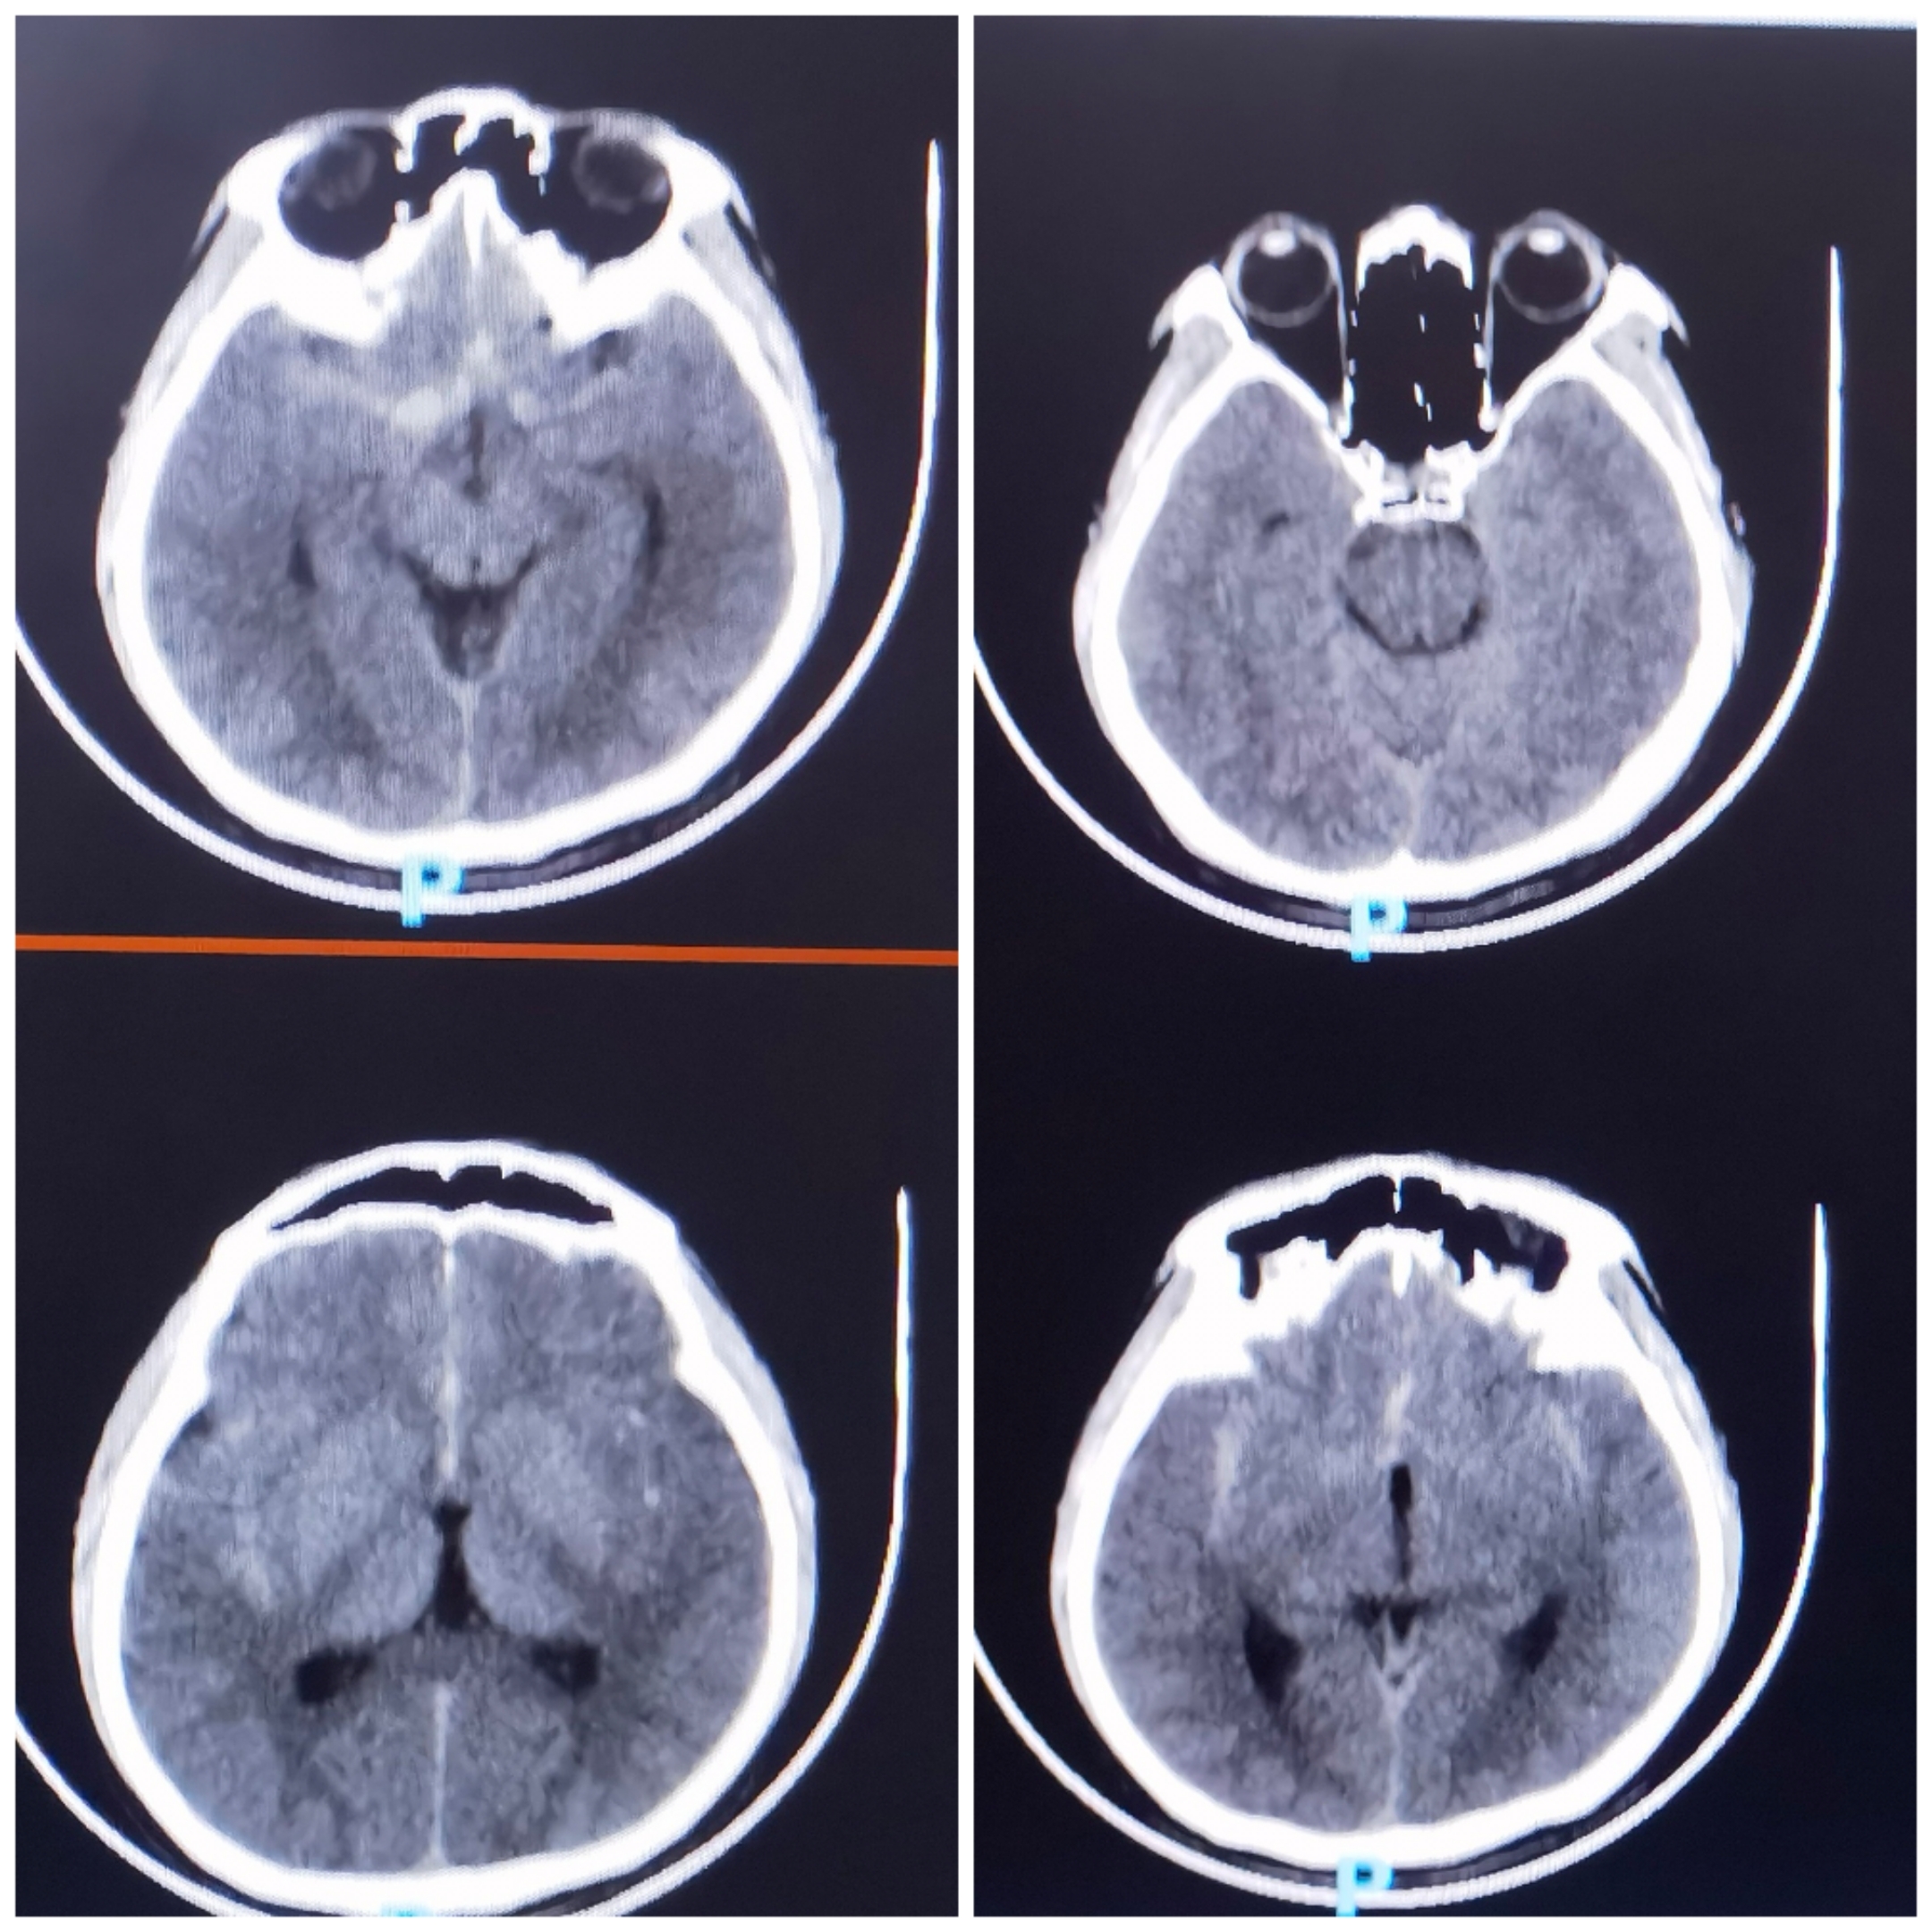

头颅CT情况:SAH

CTA提示前交通动脉瘤,双侧A1发达,似乎是宽颈的